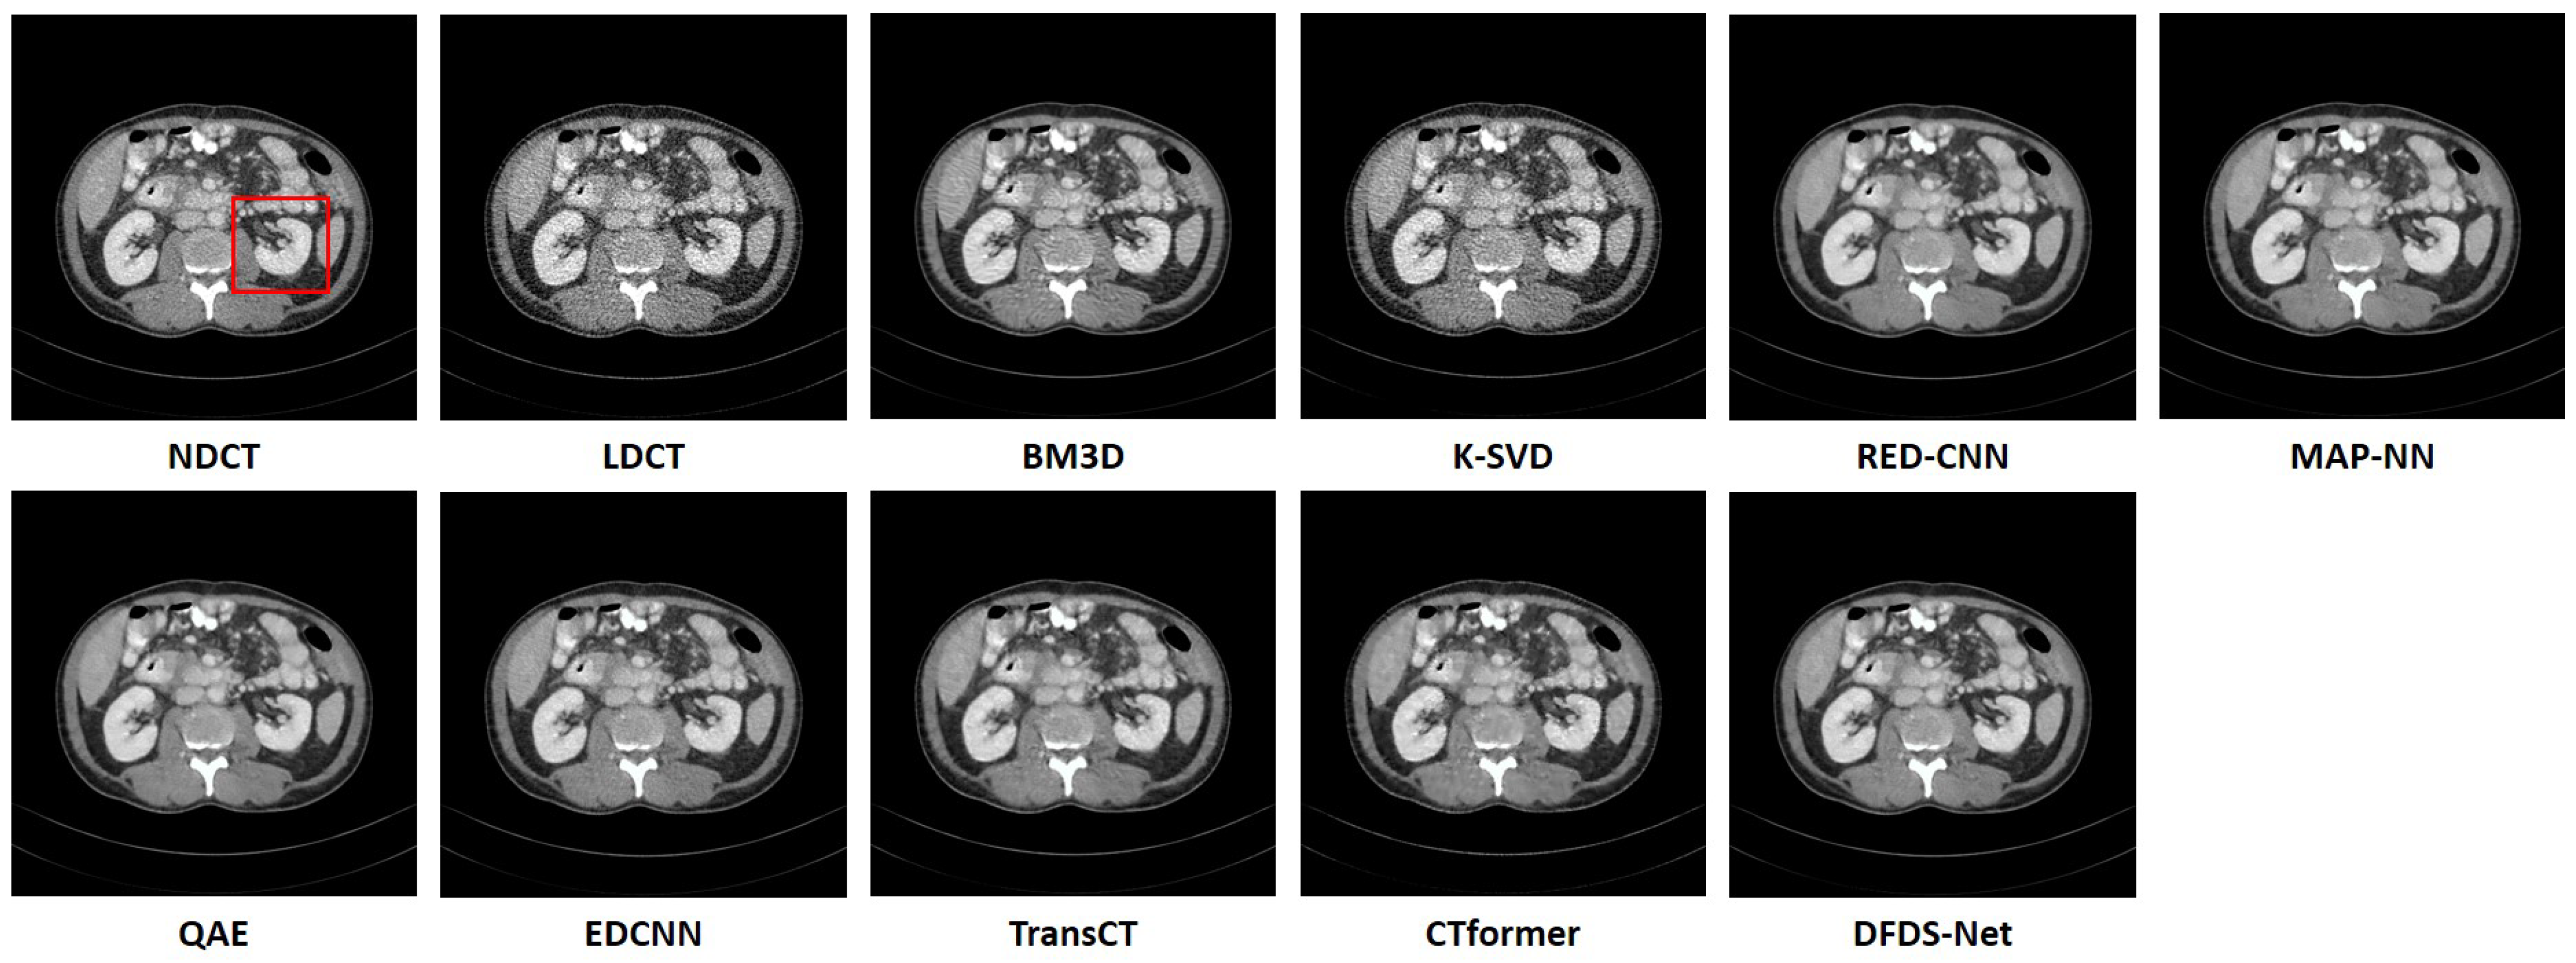

The right section of Table 6 presents the experimental results conducted on the abdomen CT dataset, where our proposed model demonstrated superior performance. Figure 9 offers a qualitative comparison of noise reduction in abdomen CT images. K-SVD showed the least effective noise reduction, with its outputs retaining significant noise distributed throughout the organs. Similar to findings in the head and chest datasets, images denoised by BM3D, TransCT, and CTformer exhibited minor noise spots. In addition, other compared methods, while displaying lower noise levels and better evaluation metrics, still faced the issue of blurriness. In contrast, the proposed model trained with the compound loss not only attained higher metric values but also minimized image error, thereby restoring clear feature details. All these fine details could be more obviously observed in the zoomed images of Figure 10. The evaluation metrics for the images in Figure 9 are detailed in the right section of Table 7.

Figure 9. Comparison of the qualitative performance of WaveletDFDS-Net and other well-known low-dose CT denoising methods on the abdomen dataset. The display window is [−160, 240] HU.

Figure 10. The zoomed images over the region of interest (ROI) marked by the red box in Figure 9. (a) BM3D, (b) K-SVD, (c) RED-CNN, (d) MAP-NN, (e) QAE, (f) EDCNN, (g) TransCT, (h) CTformer, (i) WaveletDFDS-Net.